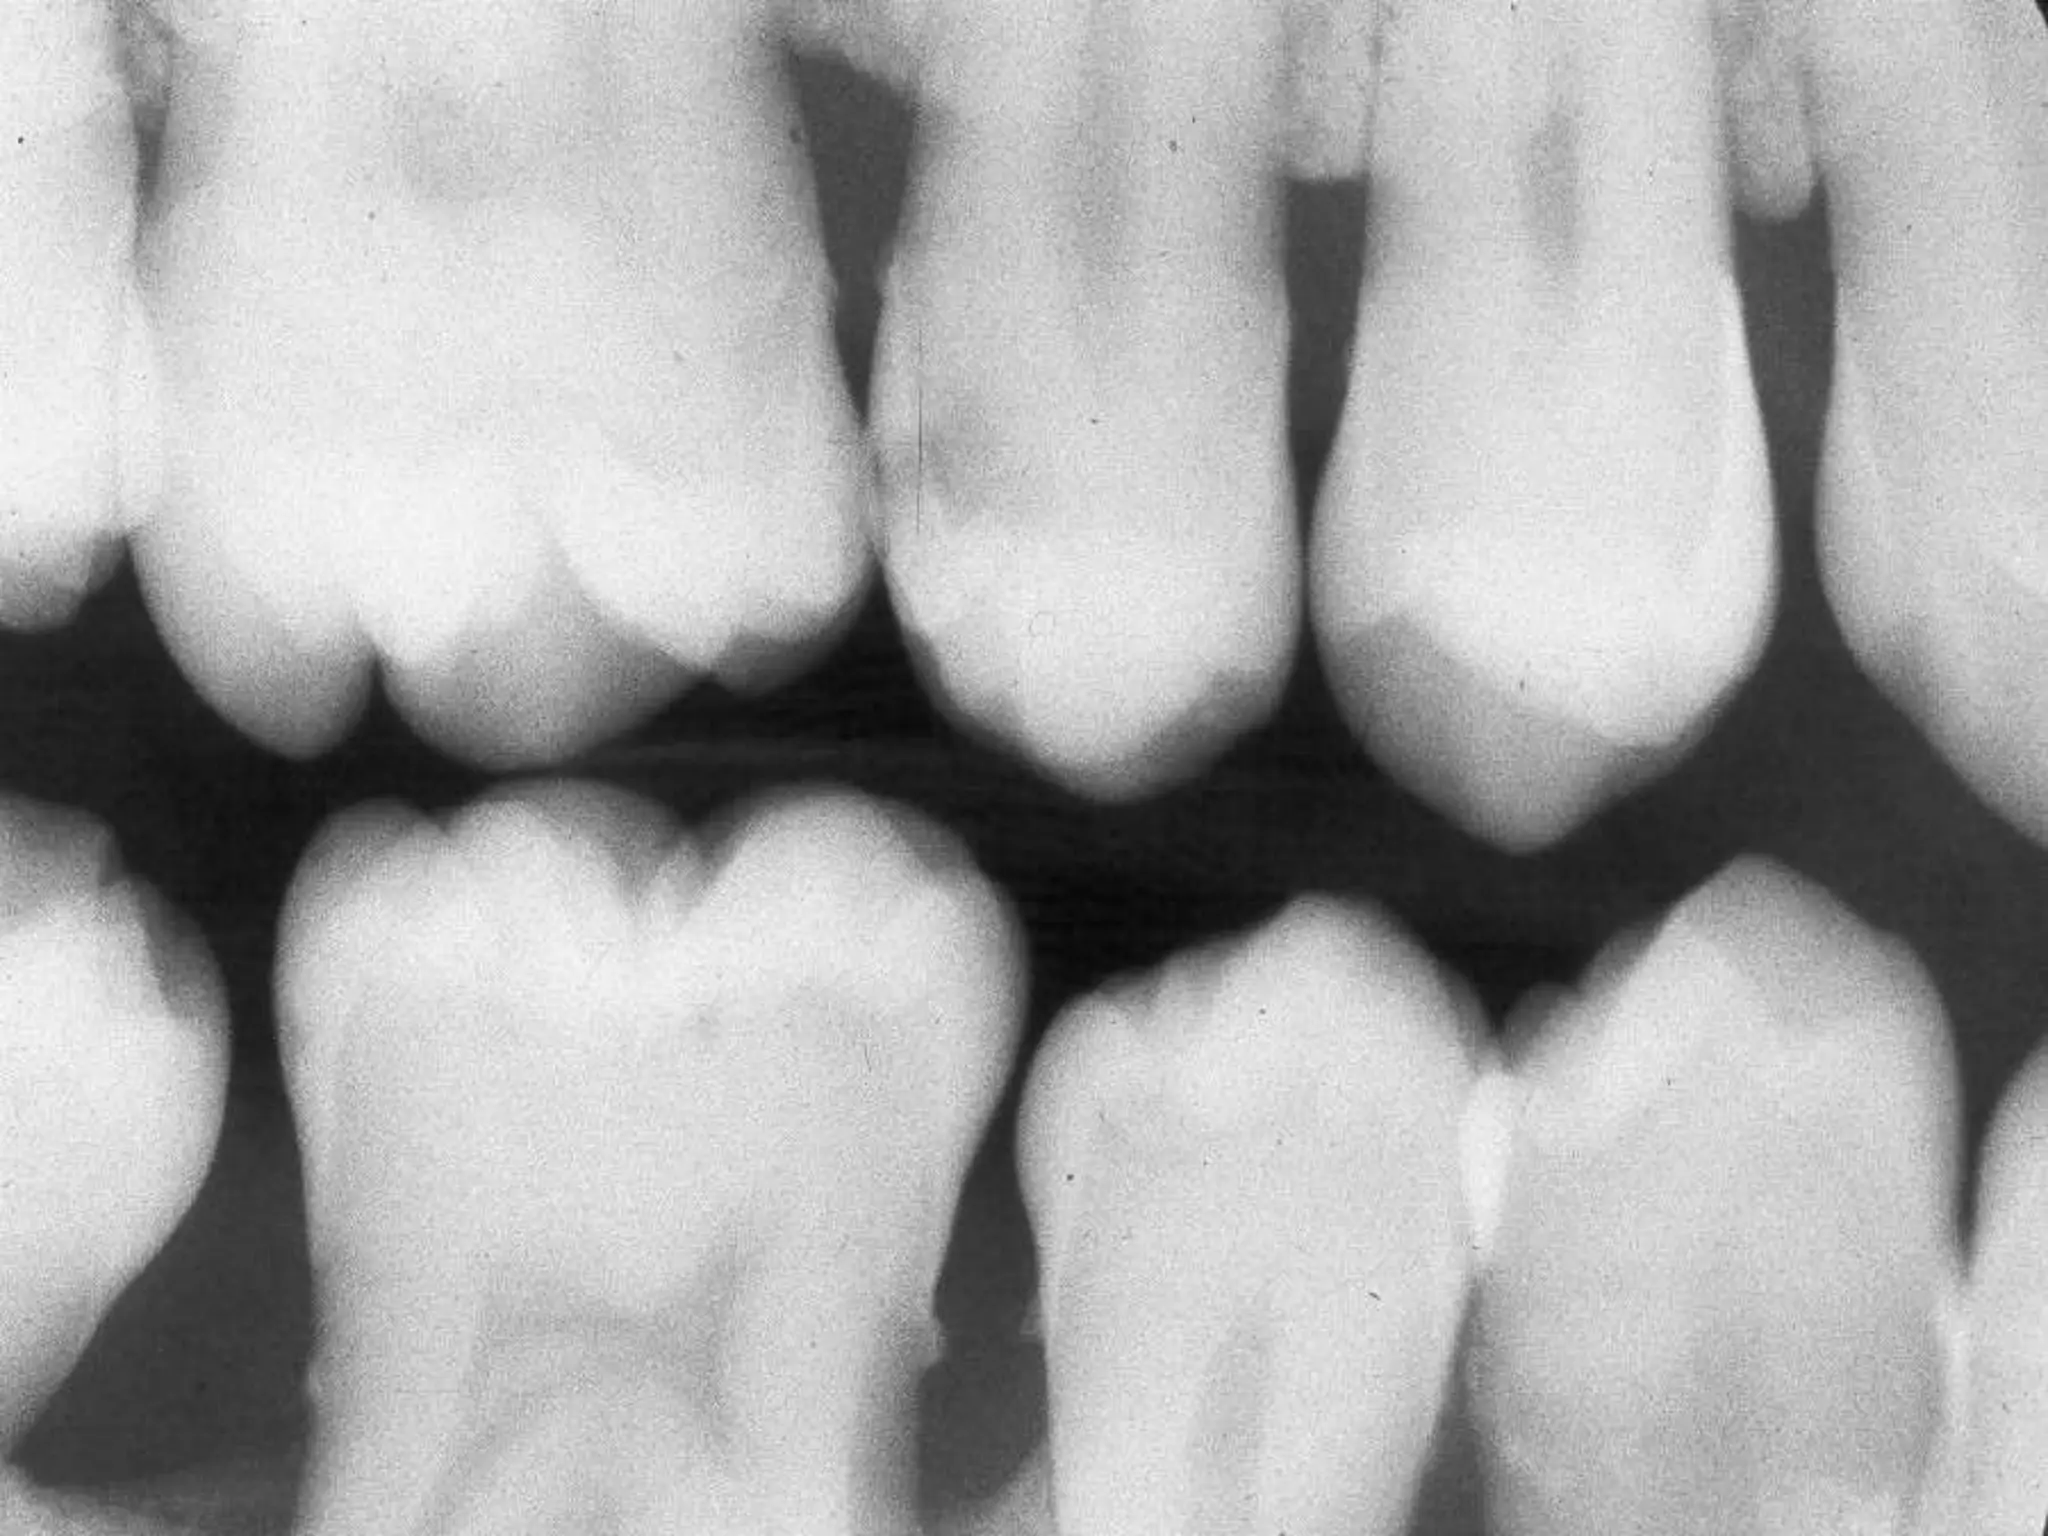

Periodontitis

Normal Anatomy:

Alveolar crest corticated

1-1.5 mm from crest to CEJ

Parallel to line between CEJ’s

Crest is pointed anteriorly

Corticated alveolar crests

CEJ

1-1.5 mm

Alveolar crests more

pointed anteriorly